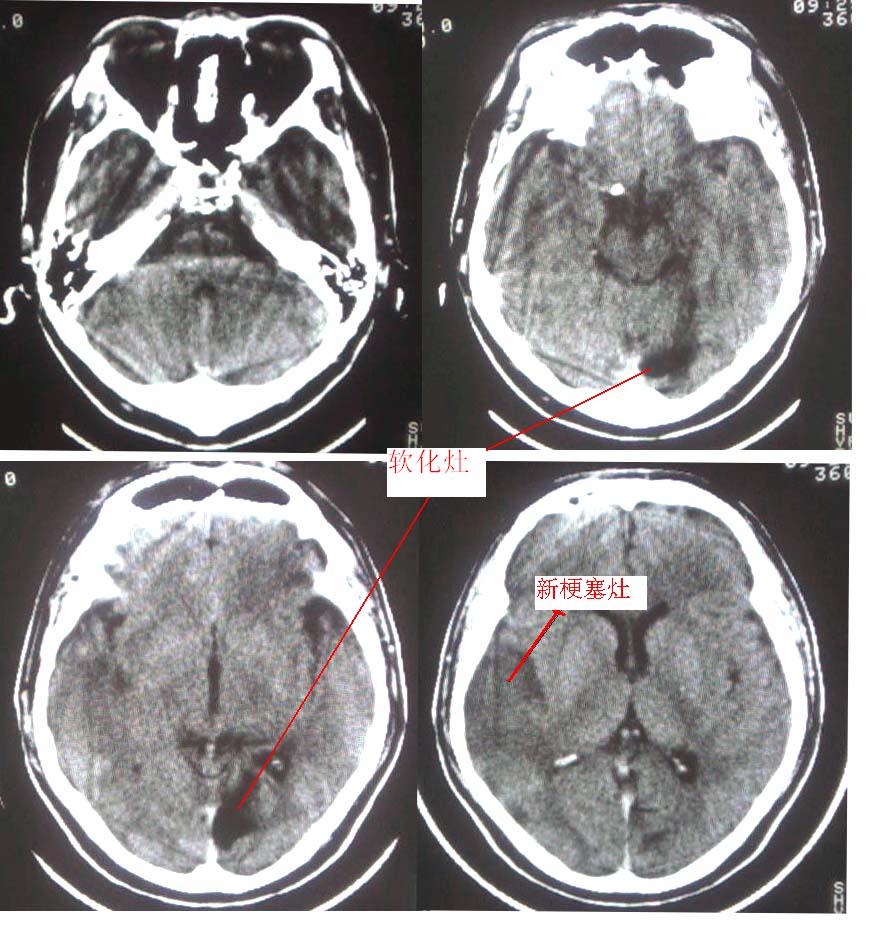

这是一个49岁 男性患者,近两天头痛,自感言语不利。既往有脑梗塞病使。麻烦各位老师看看有没有新的病灶。谢谢!

是新发病灶,另外左枕叶可见软化灶形成.

是新发病灶,另外左枕叶可见软化灶形成

右侧颞叶的低密度应考虑是新发病灶。